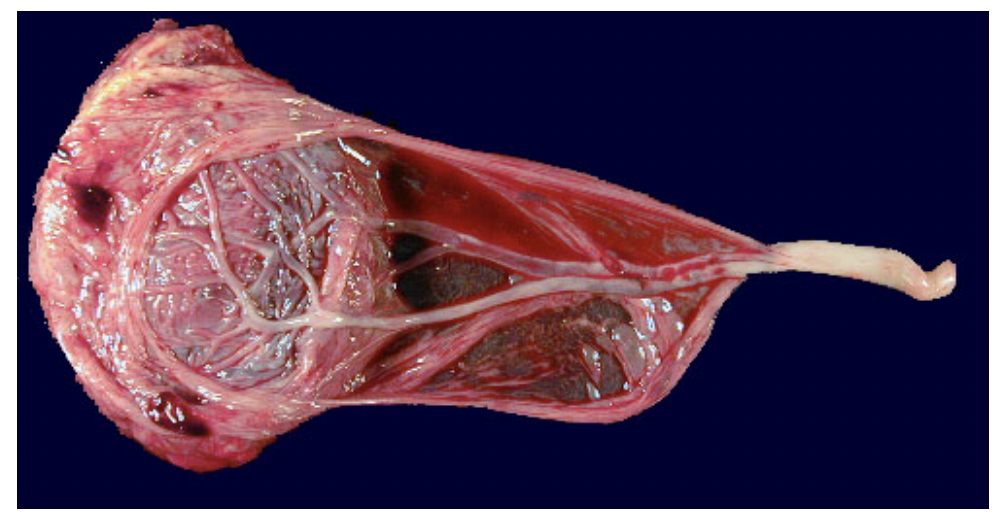

What is meant by velamentous insertion of the umbilical cord?

What condition is this associated with?

What is vasa previa and how can it be detected prior to birth?